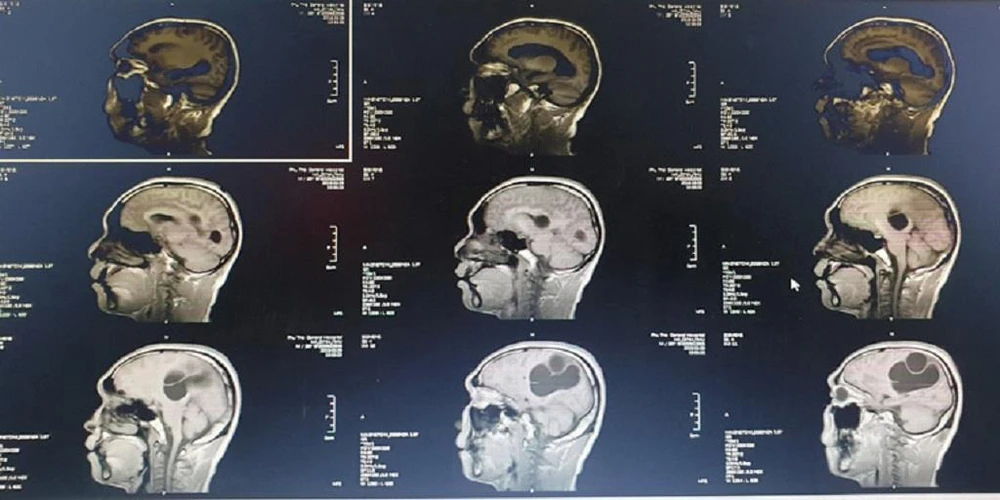

Tại BV Đa khoa tỉnh Phú Thọ, người bệnh được chỉ định chụp Citi sọ não, kết quả cho thấy ổ sán não khổng lồ ở bán cầu trái và vùng thái dương đỉnh phải. Phù não đè đẩy đường giữa. Bệnh nhân được chỉ định can thiệp ngoại khoa cấp cứu vào lúc 23 giờ ngày 9-3.

Hình ảnh CT , MRI sọ não kén sán não trước mổ. Ảnh: BVCC